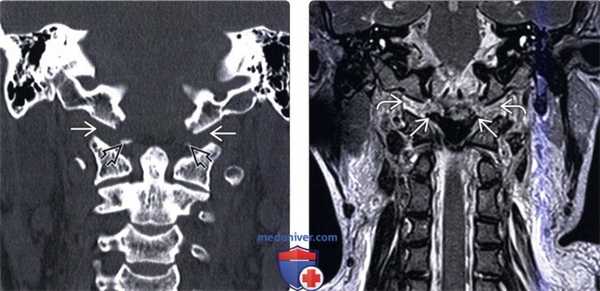

(Слева) КТ, аксиальный срез: отрыв правого мыщелка затылочной кости, фрагмент которого ротирован и смещен вниз и медиально, располагаясь над зубовидным отростком.

(Справа) На фронтальном КТ-срезе у этого же пациента определяется отрыв правого мыщелка затылочной кости, который смещен вниз и медиально и располагается над верхушкой зубовидного отростка.

(Слева) КТ фронтальный срез (костный режим): симметричные двусторонние отрывные переломы мыщелков затылочной кости, при этом фрагменты мыщелков располагаются ниже и позади основной части мыщелков. Здесь же отмечается расширение суставной щели атланто-затылочных суставов, что свидетельствует о наличии атланто-затылочной дислокации.

(Справа) На фронтальном КТ-срезе показана часть оскольчатого перелома затылочной кости в той зоне, где он распространяется на край левого мыщелка затылочной кости и подъязычный канал.

(Слева) КТ, фронтальный срез: расширение суставных щелей атланто-затылочных суставов (АЗС). Небольшие костные фрагменты представляют собой отрывные переломы нижне-медиального края мыщелков затылочной кости. Переломы в области прикрепления связок эквиваленты разрыву этих связок и только усиливают выраженность нестабильности КВС.

(Справа) Т2-ВИ, фронтальная проекция: расширение и гиперинтенсивность сигнала обоих АЗС. Также здесь видно нарушение непрерывности обеих крыловидных связок.